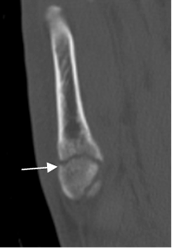

Fig 50 B. Fractura del 5º metatarsiano.

TAC reconstrucción coronal. Fractura no desplazada en el tercio proximal del 5º metatarsiano.